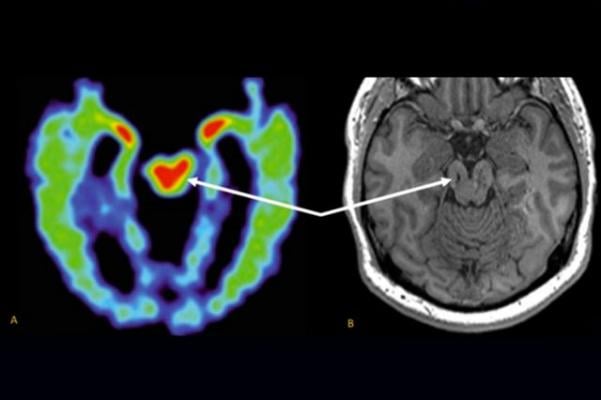

Researchers are trying to develop other methods for diagnosing CTE in the living, including positron emission tomography (PET) scans based on radioactive tracers that bind to tau aggregates. But an MRI-based method, which uses no radioactive materials, would be safer and less expensive, Merrill said.